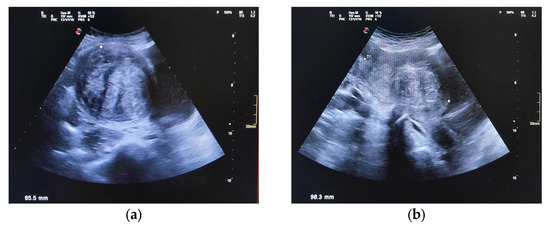

| ~July 2025 | Postoperative follow-up at 40 days: symptoms resolved; normal ultrasound; no pelvic pain or urinary issues. |